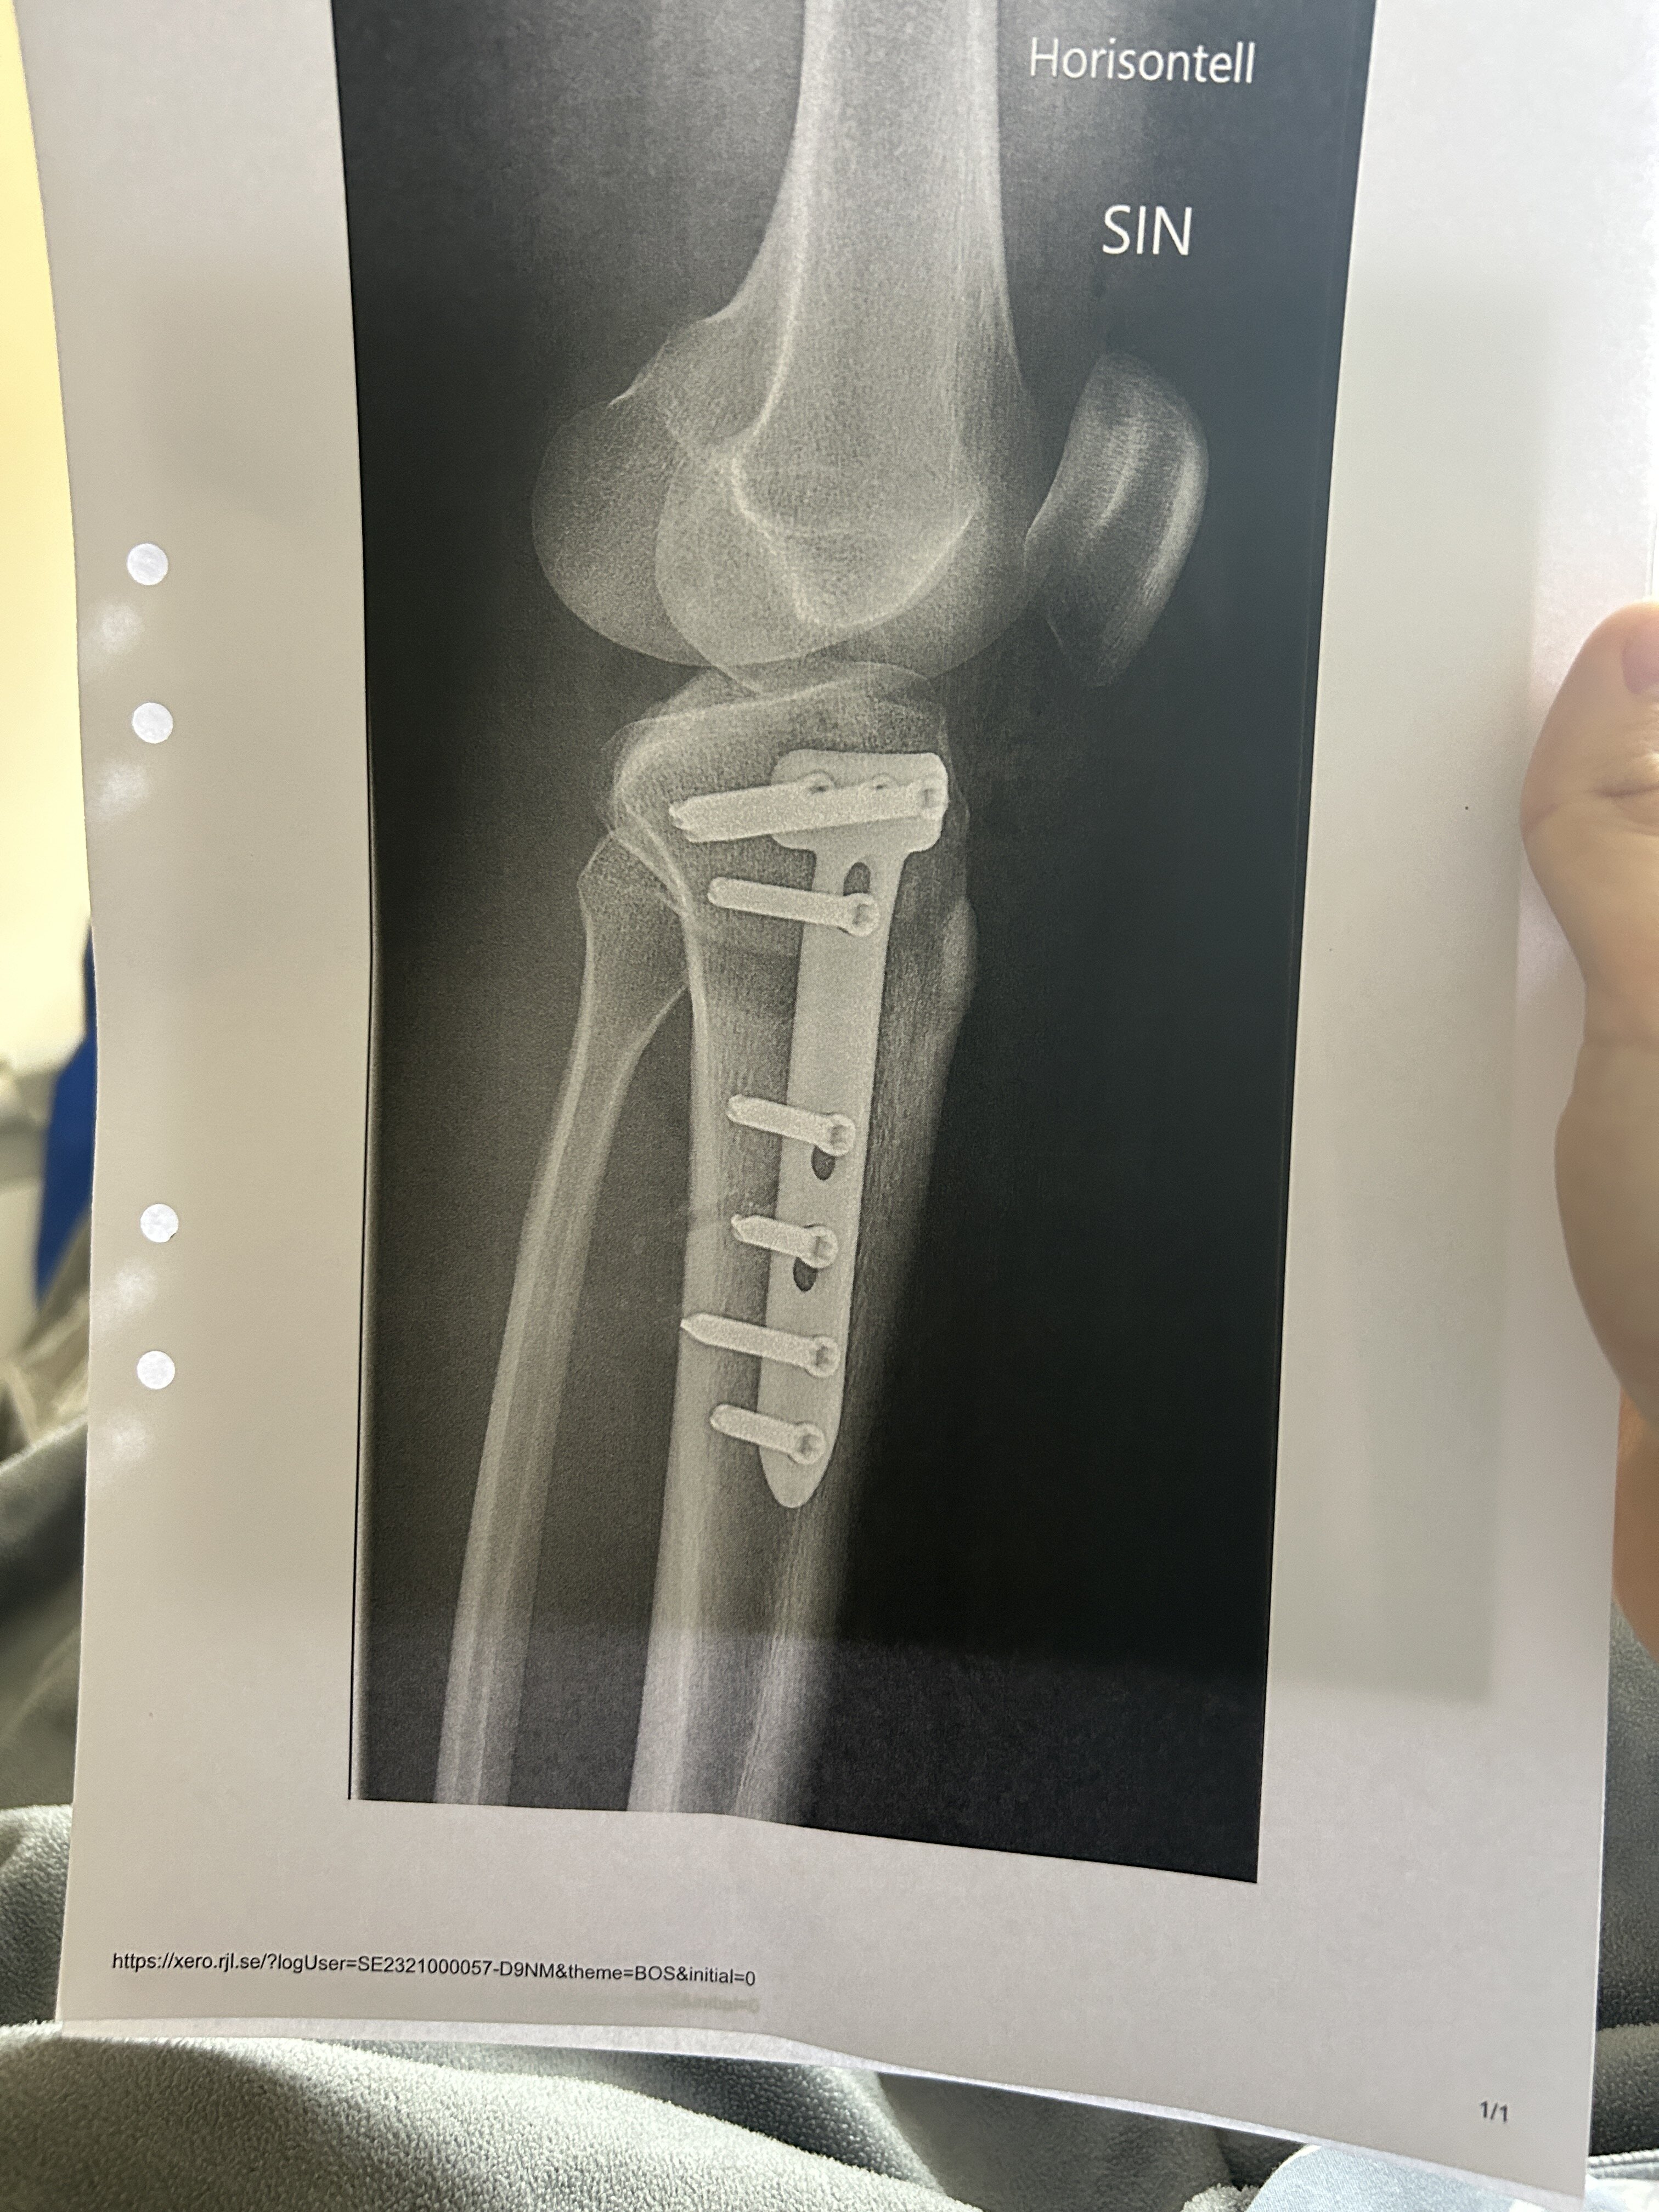

Again i dont have a clear photo of my leg but heres the x ray scan they took 20min ago. YOU GOTTA RESPECT THE DEDICATUON, i JUST got out of surgery and the first thing im doing is posting on org

After:

So yea they cut the bone right under my knee and angled it so that it would be straight, then screwed metal plates on it. The plate is on the INSIDE of my knee btw, so yea pretty cool, btw for anyone wondering you dont really gain that much in height, i havent seen myself if im taller because my leg is COMPLETELY numb but ill tell yall if i even get taller, this was more to fix the biggest failo in my body appearance. The photo doesnt show it enough but my legs are the first thing you notice when im in shorts for example. Ill be posting a video later talking about the surger because some pretty fun stuff happened hahahah. Oh i just remembered heres an MRI scan of my knee BEFORE: